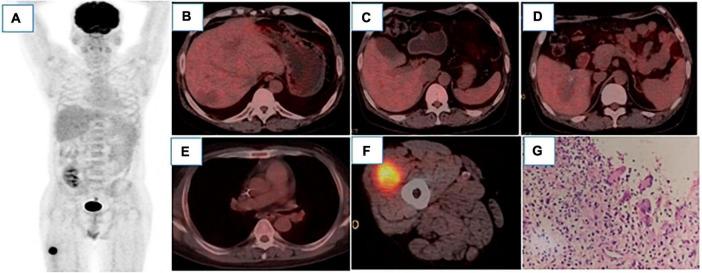

Renal transplantation is undoubtedly an effective treatment for patients with end-stage renal disease, but it is certainly not a cure. Patients require lifelong immunosuppression to maintain optimal allograft function, and post-operative risk complications such as cancer in the transplant recipient cannot be ignored. Besides, infection is a silent complication that follows transplantation. Relatedly, herein, we present a report of a 40-year-old patient who underwent renal transplantation and promptly developed a diffuse large B-cell tumor in the liver and Aspergillus infection in the trachea. In addition, an inflammatory necrotizing granuloma was also observed in the muscles. Of importance, we also described the potential of 18F-FDG-PET/CT, which was instrumental in monitoring and evaluating these relevant post-operative complications in this rare case.